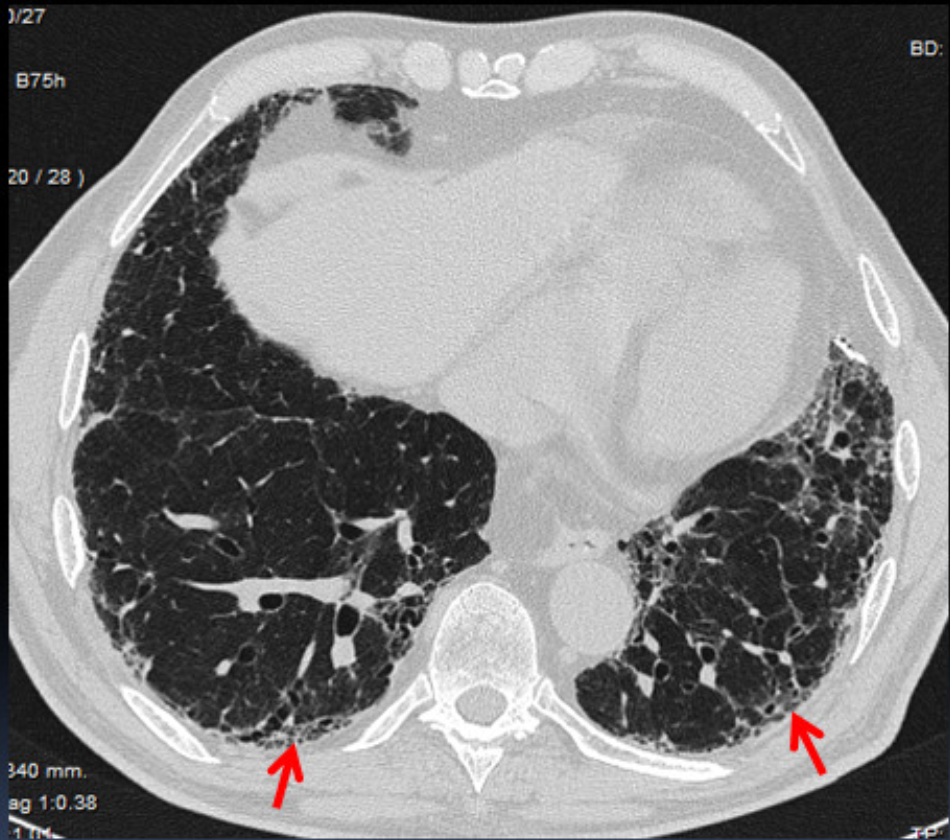

Features of Definite UIP

A

Subpleural and basal predominant

Heterogenous

Honeycombing

+- bronchiectasis

Features intermediate UIP

Subpleural/basal predominant

Subtle reticulation

Mild GGO or distortion

features don’t suggest any specific aetiology